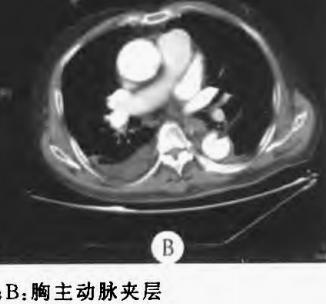

病例8

查到一篇文献,作者虽然用箭头标记了,并且是增强CT,但是鲁迅说:我大约肯定没有看出来,这是主动脉夹层!

图21